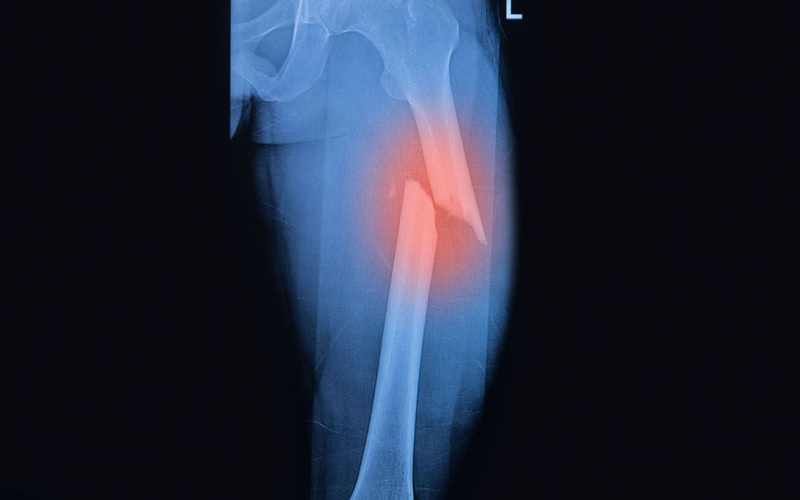

• Gãy xương: Gãy xương đùi, xương chày, xương mác, và xương mắt cá thường gặp do chấn thương.

• Nứt xương: Nứt xương đùi và xương bàn chân, thường do chấn thương hoặc căng thẳng quá mức.

mot-so-dac-diem-giai-phau-xuong-chi-duoi-4.png

Gãy xương chi dưới là bệnh lý thường gặp do chấn thương

Hiểu rõ các bệnh lý này giúp trong việc chẩn đoán và điều trị kịp thời, từ đó giảm thiểu đau đớn và phục hồi chức năng vận động hiệu quả.